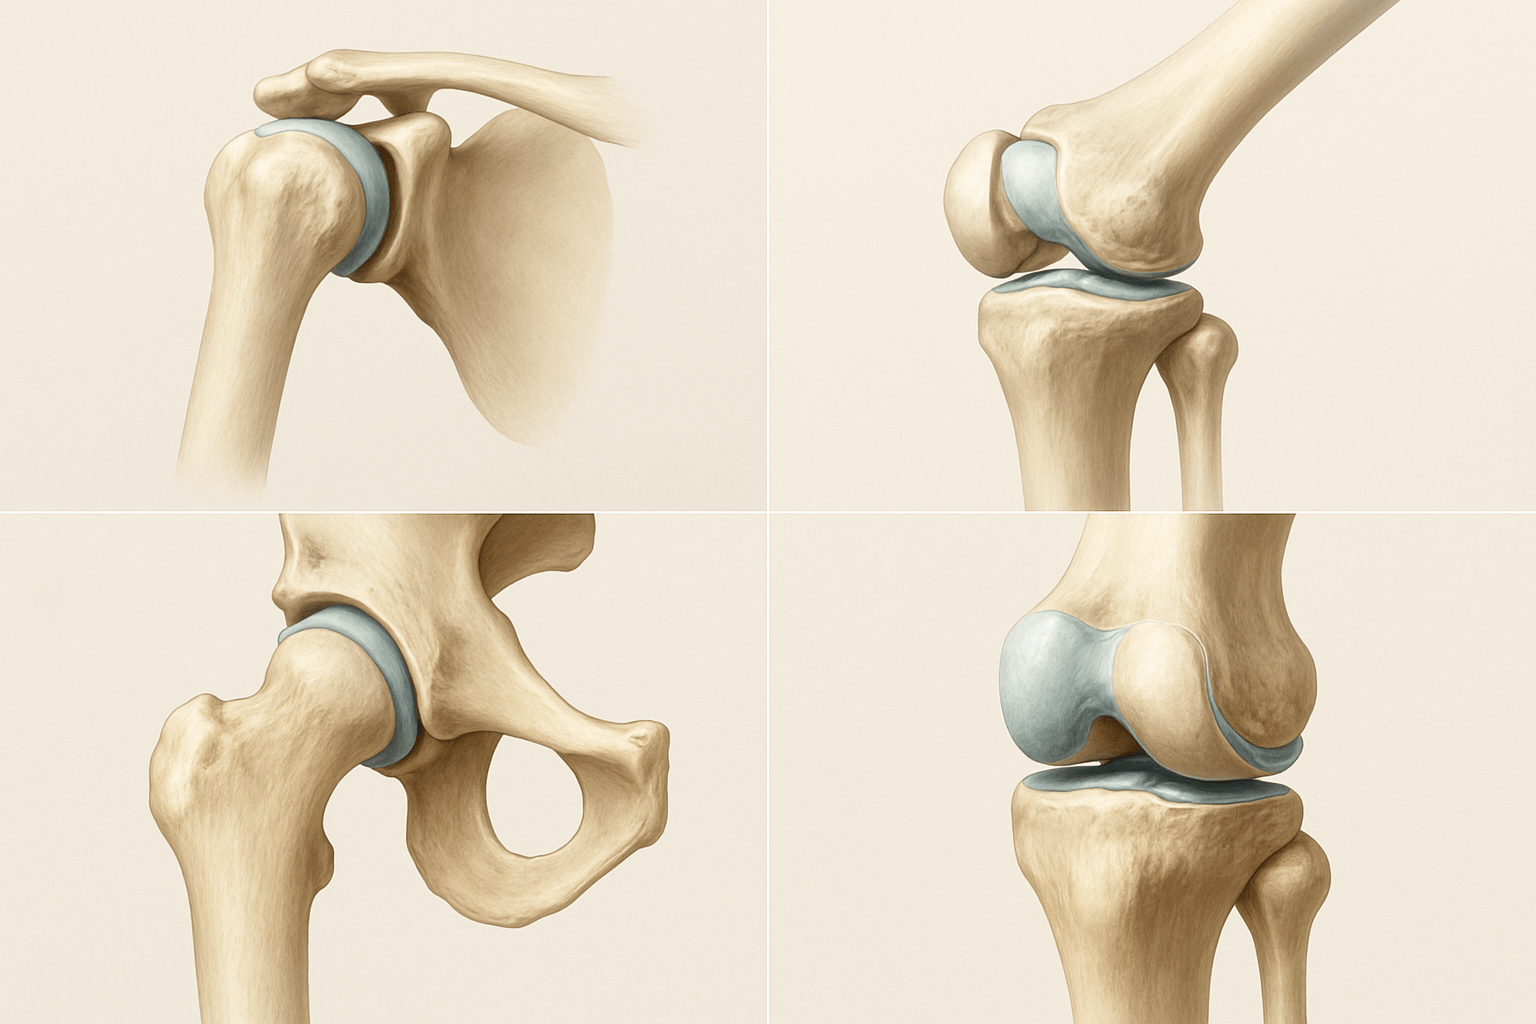

Одними из важнейших элементов опорно-двигательного аппарата являются суставы. Они представляют собой подвижные костные соединения, благодаря которым человеческий скелет способен к подвижности. С их помощью наше тело может выполнять различные движения: сгибание, разгибание, повороты, вращения, приведение, отведение. Движение тела человека начинается, прежде всего, с движения суставов. Именно поэтому так важно поддерживать их в хорошем состоянии.

Концы костей, в местах их соединения, имеют специфическую форму. Одна кость по форме выпуклая, другая с углублением. Выпуклую часть кости называют головкой сустава, а которая с углублением — ямкой. Их поверхности покрыты специальной хрящевой тканью, которая уменьшает трение, выступая неким амортизатором при резких движениях.